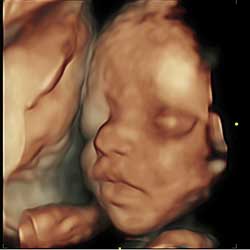

Tomorrow, our ally, Focus on the Family, will host “Alive from NY,” an unprecedented pro-life event in New York City’s Times Square. The main focus of the event will be the live broadcast of 4D ultrasounds on numerous digital screens in Times Square.

The evidence is all there in full color—hands, feet, toes, nose, eyes, ears. It is a strategy that can eventually change the minds of some of the most unlikely people who, after seeing it, cannot walk away denying that it really is a baby.

People of all political persuasions are facing the reality that we are talking about preborn humans and once you see that image, like many will tomorrow, the truth becomes undeniable.

We know the truth about life and the humanity of a baby in the womb. We know the power the ultrasound image holds. That image affects human hearts personally and has led not only to great public policy successes across the nation, but also (and most importantly) has resulted in countless lives saved. That is what makes all of the years of toil, prayers, advocacy and grassroots activism worth it!